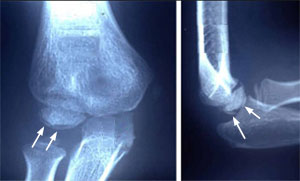

X-rays of the right elbow joint of an 8-year-old baseball pitcher show irregularity of the humerus where it meets the bones of the forearm (see arrows). This irregularity is a side effect of excessive throwing in the immature elbow.